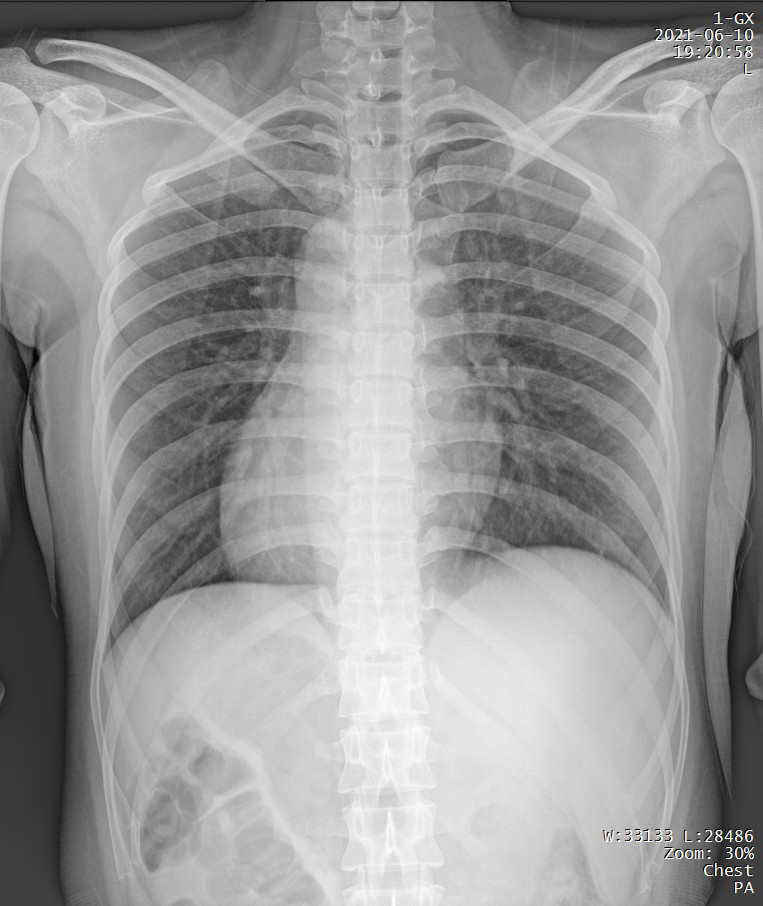

Clinical picture

臨床圖片